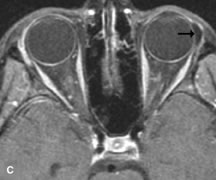

Lymphomas have MRI characteristics similar to those of inflammatory lesions in that they are hypointense to fat and isointense to muscle on T1-weighted images (Fig. 22). They may appear hyperintense to fat on T2-weighted images, perhaps owing to less fibrosis than that seen in orbital inflammatory pseudotumor, although this is not a consistent finding.31,50,66 Lymphoid tumors typically enhance moderately after contrast injection. Unfortunately, studies have shown that tumor density and homogeneity are similar between inflammatory and malignant orbital infiltrates, and MRI cannot differentiate these lesions.72,73

Fig. 22. A and B. T1- and (C) T2-weighted MR scans demonstrate a poorly defined multicompartmental mass enveloping the lateral rectus, superior rectus, and levator palpebrac superioris muscles. The lesion is isointense to brain on T1- and T2-weighted scans, as is typical for highly cellular neoplasms. D. Postcontrast fat-suppressed T1-weighted scan demonstrates intense enhancement of the infiltrating intraconal and extraconal tumor.